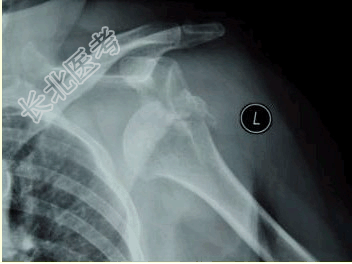

- [材料题] 患者女,58岁,左肩关节外伤,医院就诊,行X线检查,如下图。

- 多项选择题3.诊断考虑的疾病是

A、肩关节下脱位

B、肩锁关节脱位

C、肩关节前脱位

D、肱骨外科颈骨折

E、肱骨小结节骨折

F、肱骨大结节骨折